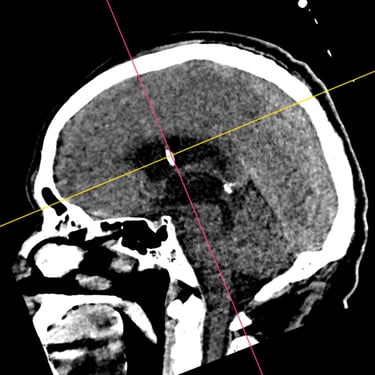

Hidrocefalia: Tratamiento mediante Derivación Ventriculoperitoneal

La hidrocefalia es una condición caracterizada por la acumulación anormal de líquido cefalorraquídeo en los ventrículos cerebrales, lo que genera aumento de la presión intracraneal y síntomas como cefalea, náuseas, alteraciones cognitivas y trastornos de la marcha. Cuando el manejo médico no es suficiente, la derivación ventriculoperitoneal (DVP) es el tratamiento quirúrgico más utilizado. Este procedimiento permite drenar el exceso de líquido desde el cerebro hacia la cavidad abdominal, donde es reabsorbido, aliviando la presión intracraneal y mejorando la función neurológica. El tratamiento oportuno es clave para prevenir secuelas.